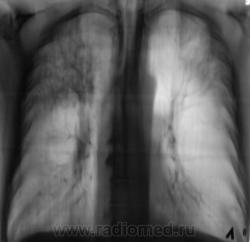

Как всегда, всё началось с "контроля" после флюорографии. Пациента дообследовали согласно стандарту.

Конечно, основная дифференциальная диагностика проводилась между пневмонией и "туберкулёзным поражением".

Но пациент жалоб не предъявляет, клиники - никакой. Коллеги клиницисты - в полной растерянности. Назначили консультацию фтизиатра.

1. Процесс двусторонний.

Архив - 2 года тому флюорография - норма.

Профанамнез - нет, не работал и не жил рядом.

Клиники - никакой, "тухлая", малосимптомная. Мы с коллегой фтизиатром, хотя душа и не лежит, "зрим в корень", как ориентирует В.Б. Серов, и потихоньку, полегоньку меняем вектор на фтизиатрический, а что делать?